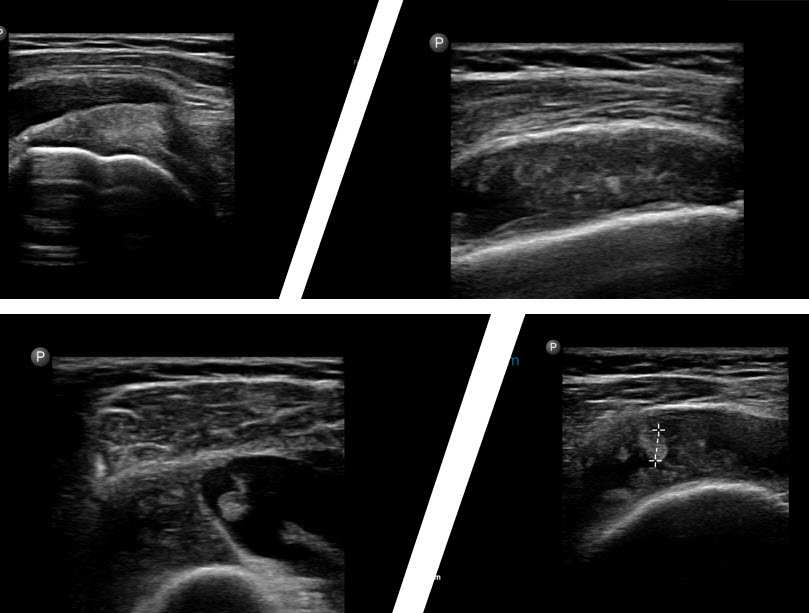

Experiența personală, susținută și de studiile privitoare la ecografia umărului, îmi permit să afirm că stația intermediară între radiografie și rezonanța magnetică este ecografia umărului.

Ecografia umărului are anumite particularități, comparativ cu alte articulații. Umărul fiind cea mai mobila articulație din corp, putem să examinăm în dinamică majoritatea structurilor umărului, fără a fi întotdeauna nevoie să folosim metode mai avansate cum este rezonanța magnetică.

Acest lucru este justificat și statistic, majoritatea patologiei umărului la pacienții fără traumatisme este dată fie de patologia coafei rotatorilor, care este vizibilă integral ecografic, fie de patologia degenerativă, care este și ea evidentă ecografic și radiografic.

Examinarea ecografică a umărului

Dupa radiografie, decizia cea mai frecventă este de a alege între ecografie și rezonanță magnetică.

Aceasta decizie se face în funcție de patologia inițială suspectată și, bineînțeles, de aspectul radiografiei. Decizia este uneori ușoară, atunci când pe examinare se vede o calcificare în spațiul subacromial, care orientează diagnosticul spre o patologie a coafei rotatorilor și prin urmare prima alegere ar fi ecografia. Dacă radiografia nu evidențiază nimic și clinica pacientului sugerează o leziune intraarticulară, rezonanța magnetică, care are posibilitatea să vizualizeze inclusiv patologia intraarticulară, este varianta mai bună.

Avantajul major al ecografiei este posibilitatea de efectua examinare în dinamică, vizualizând structurile în mișcare și permite, de asemenea, examinare focalizată exact asupra regiunii dureroase.

În cazul detecției patologiei inflamatorii intraarticulare sau intrabursale, se poate lua decizia unei intervenții minim invazive (evacuare bursita subacromială, injectare intraarticulară sau intrabursală de mix antiinflamator și analgezic) sub ghidaj ecografic.